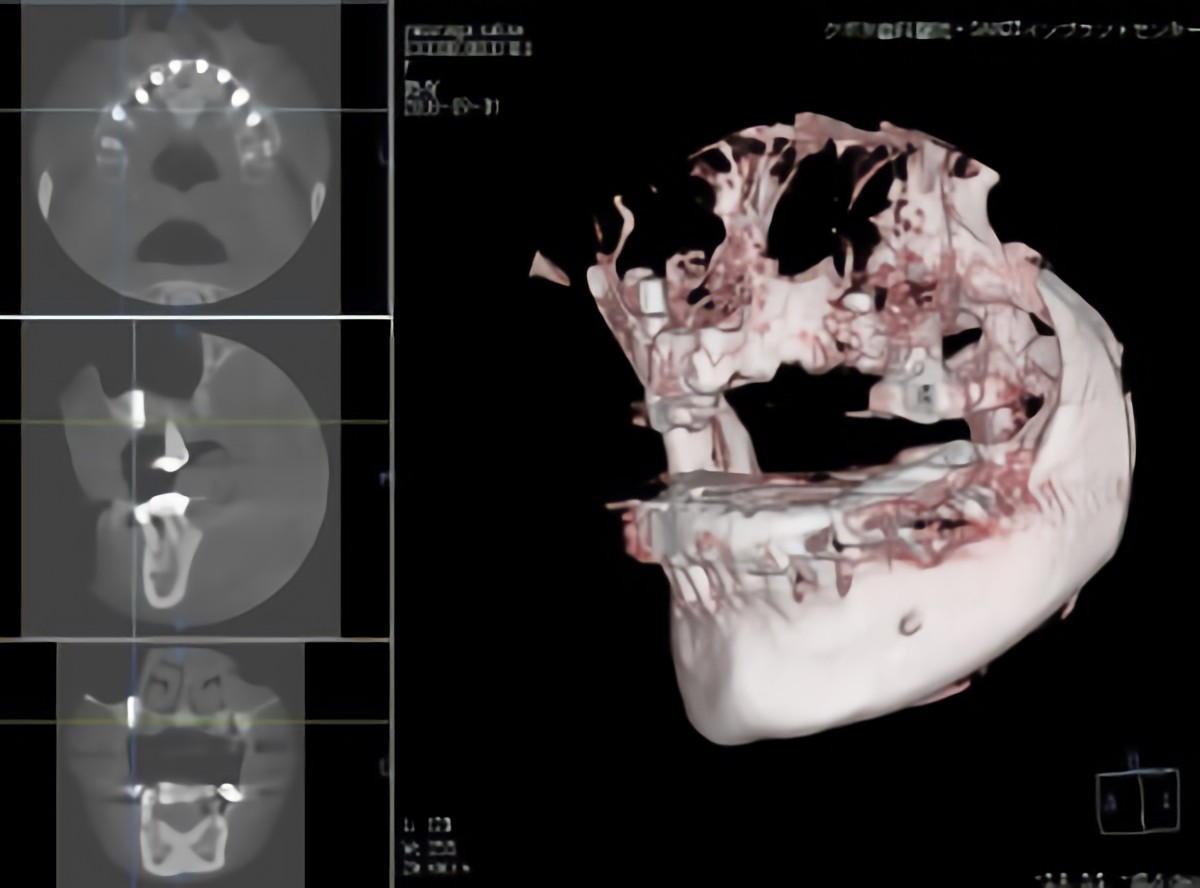

コーンビームCTの撮影画像

インプラント治療は、歯を失った部分の顎の骨に人工歯根を埋め込み、その上に人工歯を装着することで、噛む機能や見た目の回復を図る治療です。人工歯、土台となるアパットメント、歯の根の役割を担うインプラント体の三つの構造から成り立ち、天然歯に近い安定性が期待できます。埋入されたインプラントは、一定の治癒期間を経て骨と結合し、しっかり噛める状態へと導かれます。症例によっては、条件を慎重に見極めたうえで、手術後比較的早期に使用できる方法が選択されることもありますが、すべての患者様に適応できるわけではなく、十分な診査と判断が重要です。

レントゲンやCT、口腔内模型などを用いて丁寧な診査を行い、お口の状態を正確に把握します。そのうえで、診査結果をもとに治療の内容や選択肢について分かりやすく説明し、患者様が納得したうえで治療を受けられるよう心がけています。